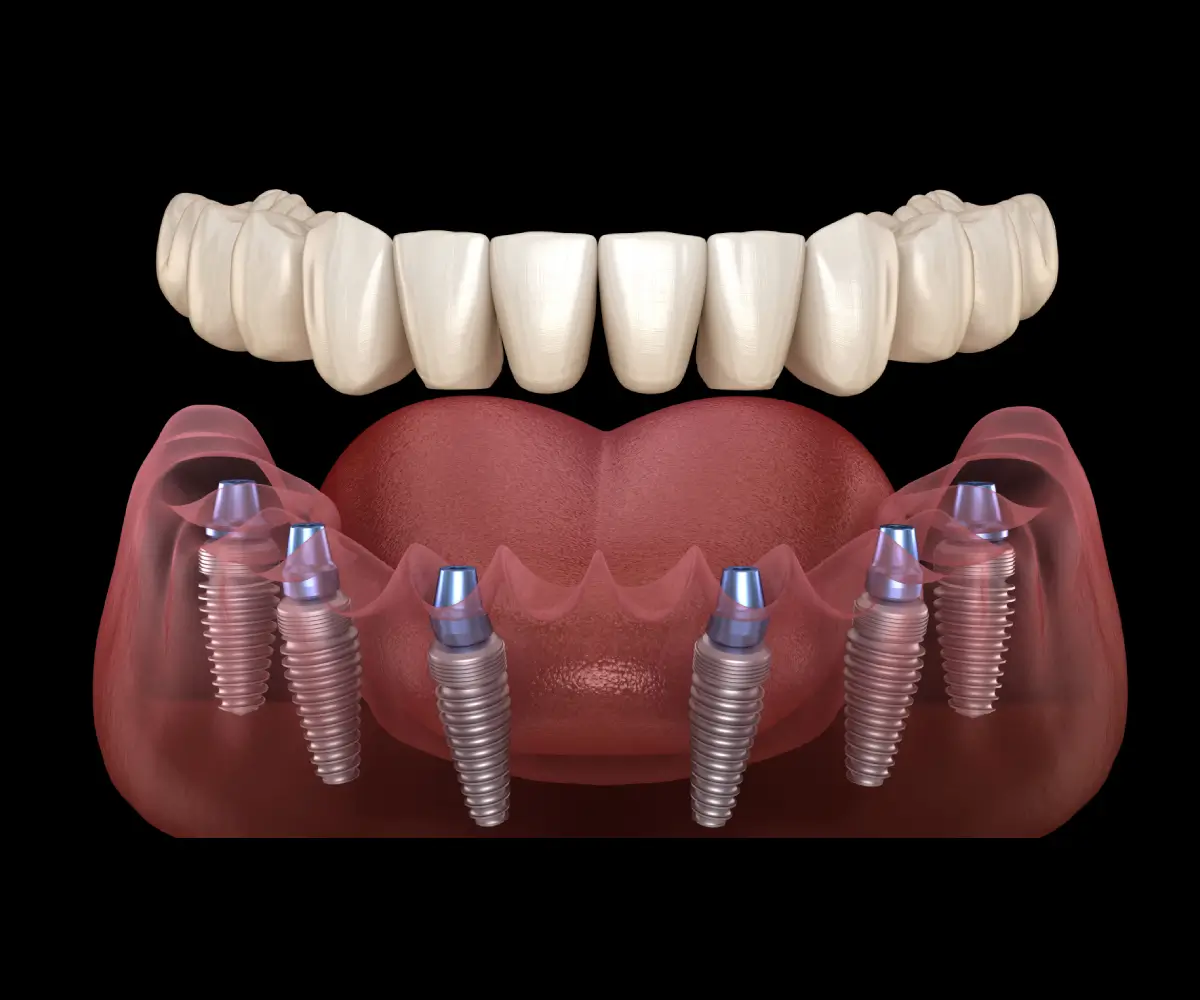

Full mouth dental implants are designed to replace all missing teeth with a stable and long-term solution. This treatment can improve chewing ability, speech, comfort, and overall confidence while restoring the appearance and function of a complete smile.